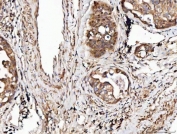

IHC staining of FFPE human lung cancer tissue with Angiogenin antibody. HIER: boil tissue sections in pH8 EDTA for 20 min and allow to cool before testing.

IHC staining of FFPE human hepatocellular carcinoma tissue with Angiogenin antibody. HIER: boil tissue sections in pH8 EDTA for 20 min and allow to cool before testing.